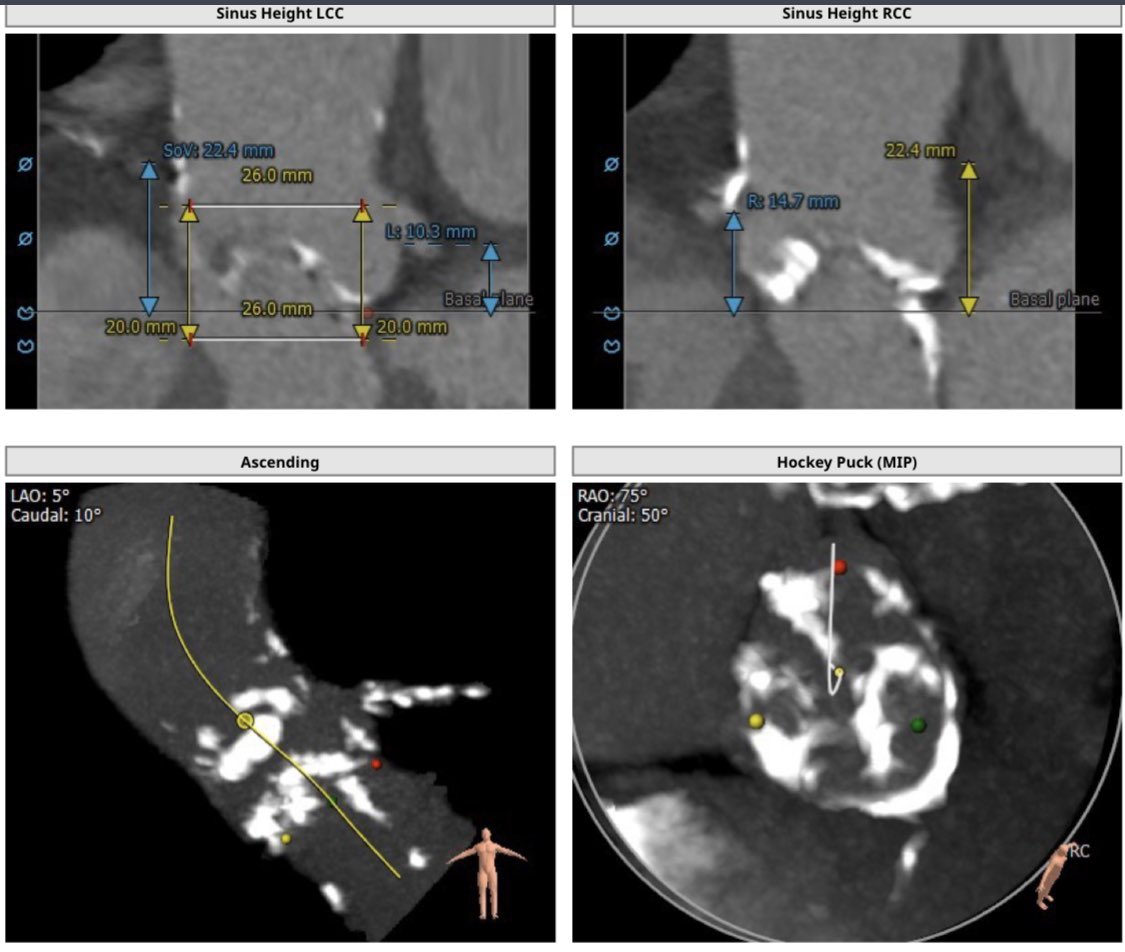

Our first #Sapien3Ultra #TAVR on the @Edwards_TAVR Commander system @MountSinaiNYC @MountSinaiHeart. Annular/LVOT Ca no PVL! Outstanding team! @KHERA_MD Samin Sharma, Annapoorna Kini, Stam Lerakis.